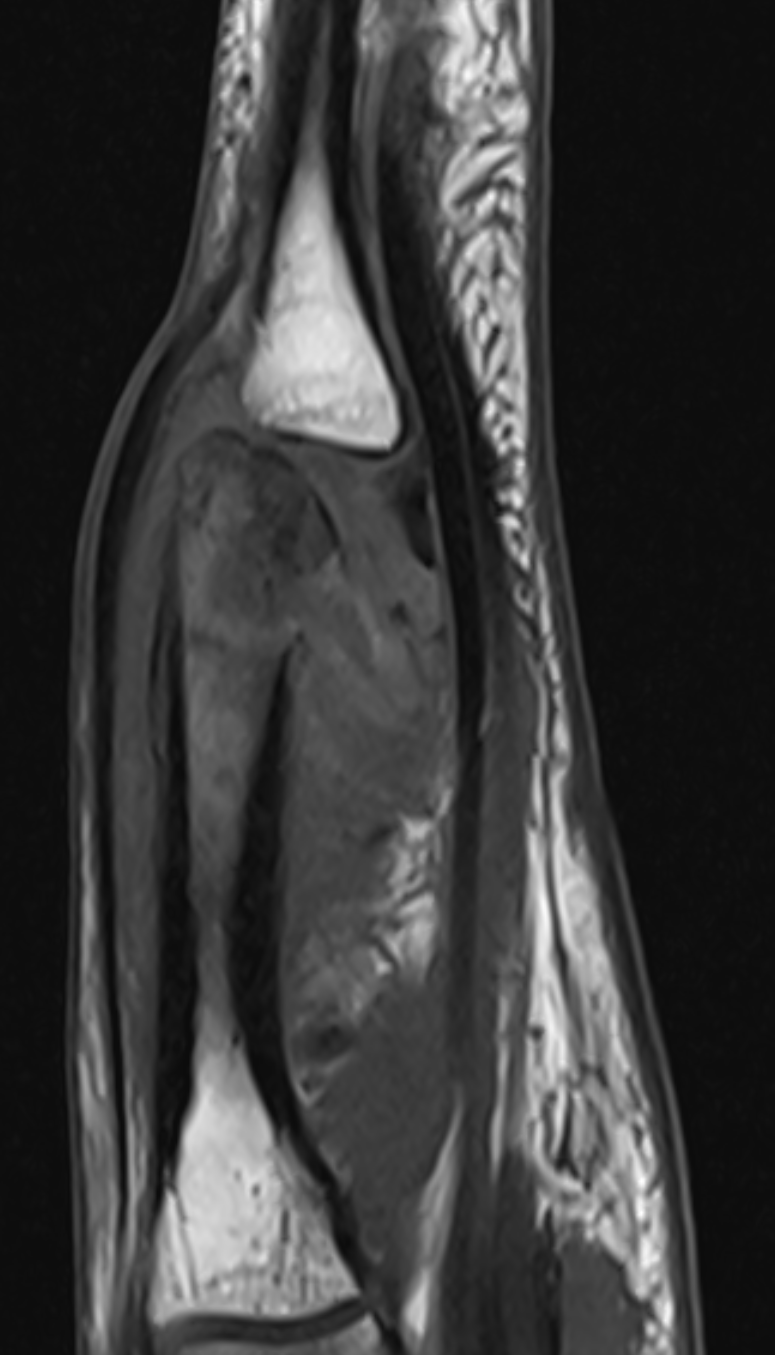

3. Osteomyelitis